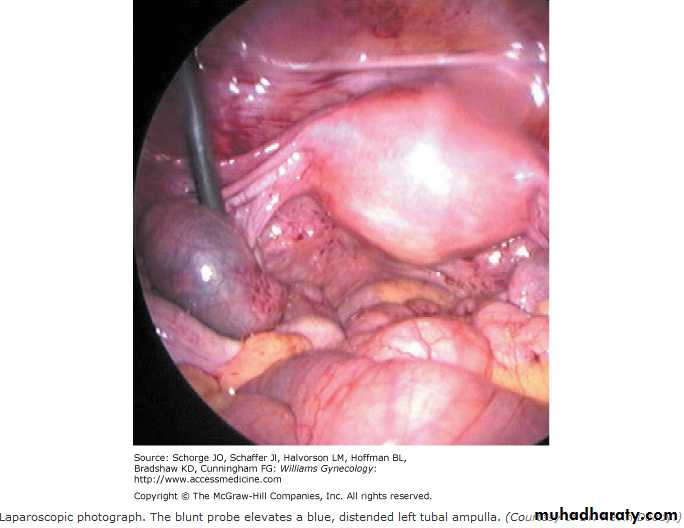

The patient have 2 miss period, she have positive B.HCG presented as acute abd. Laproscopy done for her, what is the finding?Out line the treatment options?